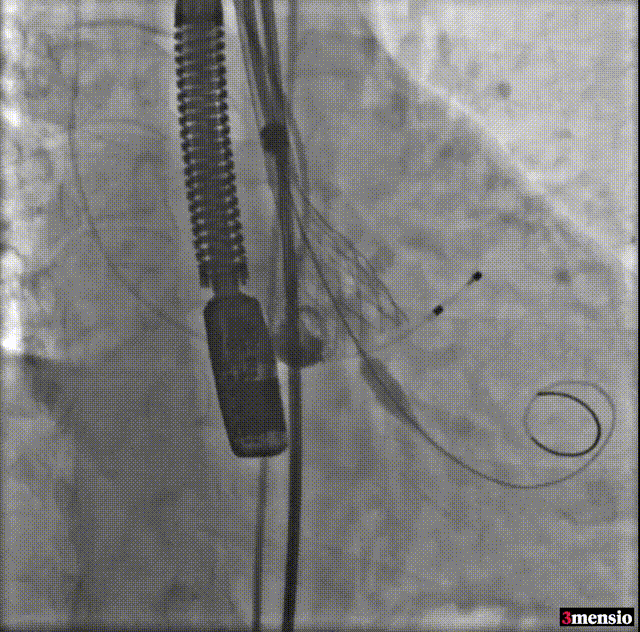

导丝跨瓣

球囊预扩

预释放定位